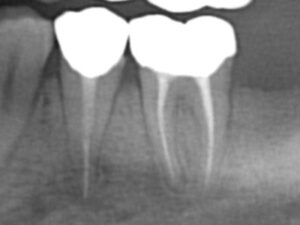

症例2

Before